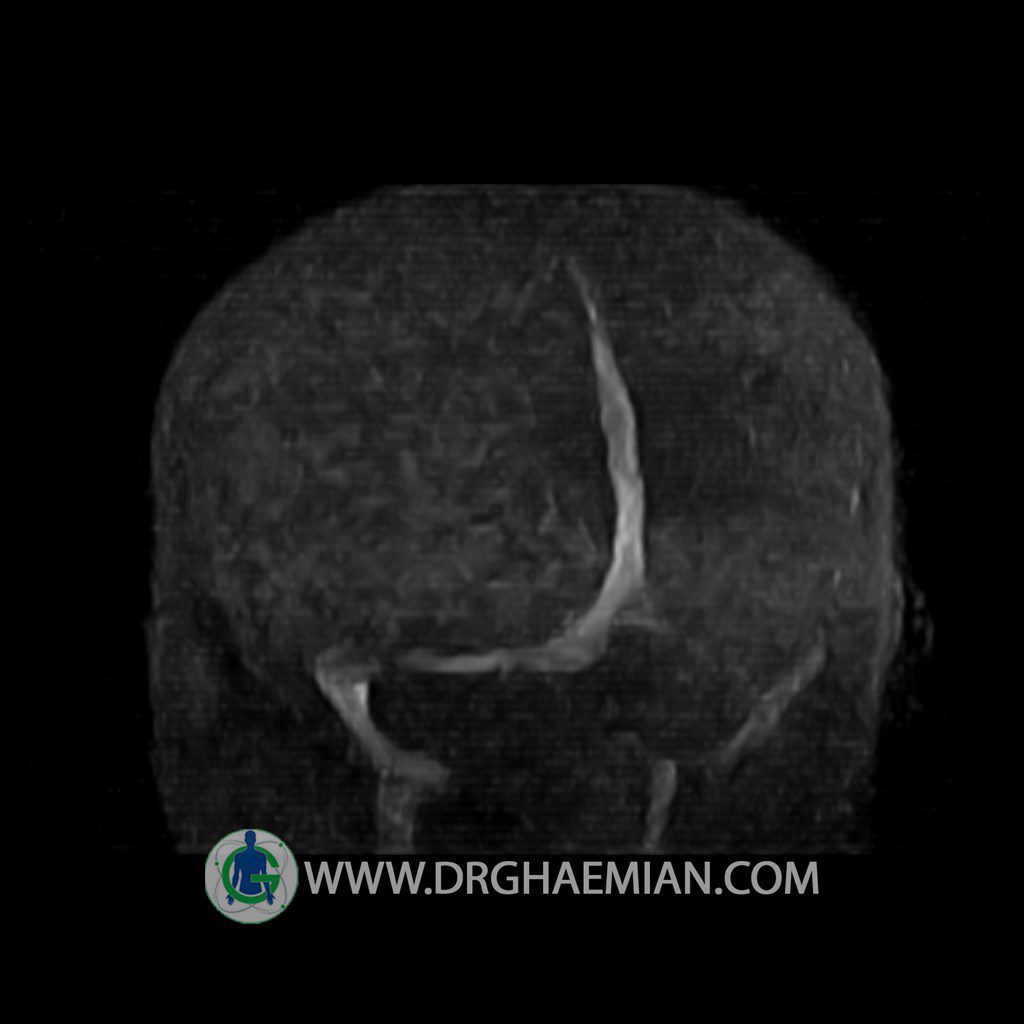

ام آر وی یک روش تصویربرداری دقیق و غیر تهاجمی است که برای معاینه ورید های بدن و ارزیابی سلامت رگ ها استفاده می شود. ورید ها خون را از اعضای بدن به قلب باز می گرداند تا دوباره اکسیژن و مواد مغذی به خون داده شود. ام آر وی جریان خون را ارزیابی و موارد غیرعادی مضر مانند لخته های خونی را شناسایی می کند. در این کیس ترومبوز دیواری مغز در سینوس عرضی راست و ترمبوز جزئی در سینوس عرضی چپ دیده می شود.

Technique: TOF ( time of flight ).

Images of the venous cranial vessels demonstrates a superior sagittal sinus of normal caliber with normal arrangement of draining superficial cerebral veins.

– Narrowing of left transverse sinus with filling defect & inthimal irregularity

suggestive for partial thrombosis

– Inthimal irregularity in anterior wall of right transverse sinus suggestive for mural thrombosis

are seen